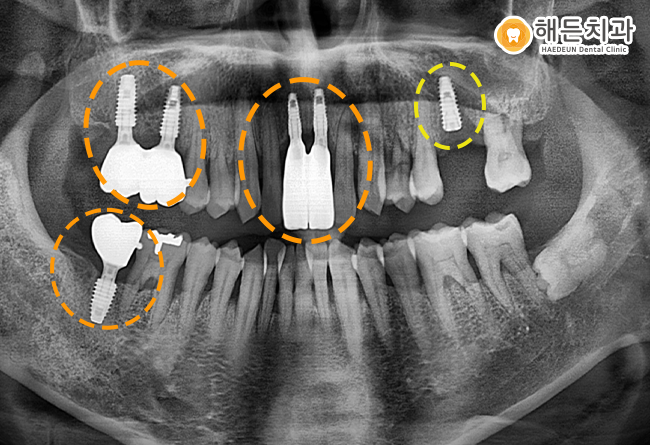

픽스처가 잇몸뼈에 잘 유착할 수 있도록 충분히 기다려준 후,

임플란트 머리 역할을 하는 크라운을 올려주어 마무리하였습니다.

오른쪽 임플란트를 마무리하여 오른쪽으로 식사가 가능하게끔 도와드린 후, 왼쪽 위의 임플란트 치료를 시작하였답니다.

.

왼쪽 위의 임플란트도 치료가 잘 마무리 될 수 있도록 신경 써 치료를 도와드리기로 하였습니다.